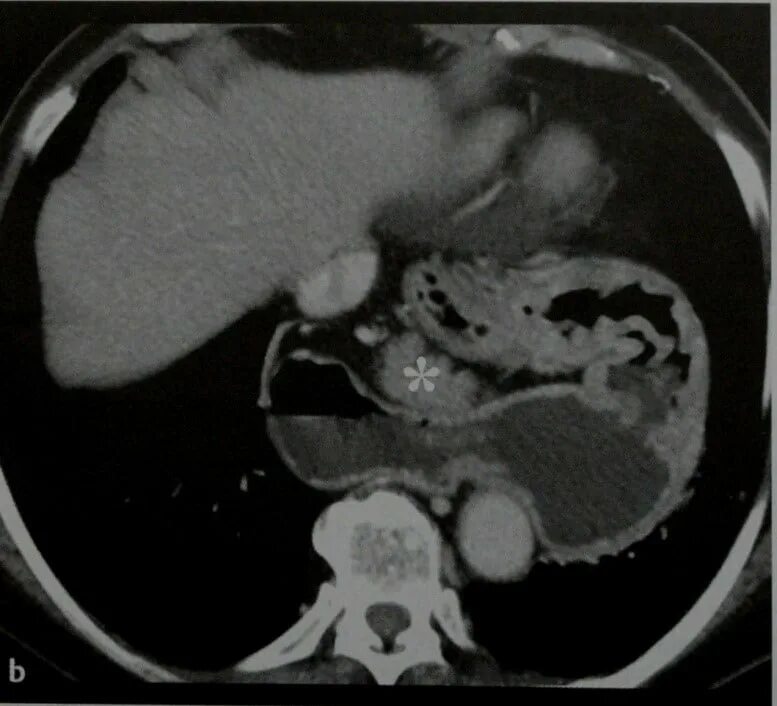

Грыжи на кт